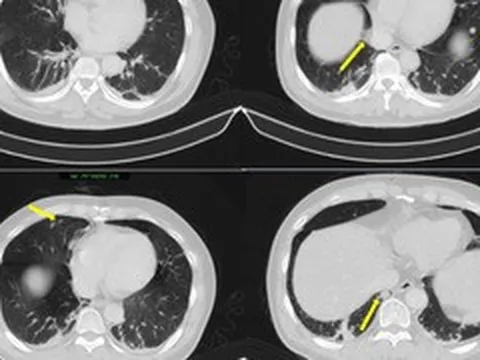

Trong quá trình phẫu thuật, khối u xơ có kích thước lớn, dính chặt vào nhiều cơ quan trong ổ bụng như phúc mạc, mạc nối lớn và quai ruột non. Đặc biệt, hệ thống mạch máu nuôi khối u tăng sinh mạnh, trong đó có những mạch máu đường kính lên đến 7 mm, cùng nhiều dải dính phức tạp, làm tăng đáng kể nguy cơ chảy máu và biến chứng trong mổ.

E-kip phẫu thuật đã lựa chọn đường mổ dọc để đảm bảo bộc lộ tối đa trường mổ, tạo điều kiện xử trí an toàn khối u kích thước lớn. Trong quá trình bóc tách khối u có hệ thống mạch máu tăng sinh phức tạp, các bác sĩ đã chủ động áp dụng kỹ thuật cầm máu bằng mũi may hình chữ nhật linh hoạt và hiệu quả.

Kỹ thuật này giúp kiểm soát tốt các điểm chảy máu lan tỏa trên diện rộng, đặc biệt tại vùng diện cắt và các vị trí mạch máu nuôi lớn, từ đó hạn chế tối đa mất máu trong mổ.

Kết thúc ca mổ, khối u đã được bóc tách hoàn toàn mà không gây tổn thương các tạng lân cận. Đặc biệt, tử cung của người bệnh được bảo tồn thành công, đây là yếu tố có ý nghĩa rất lớn đối với một bệnh nhân còn trẻ và chưa hoàn thành kế hoạch sinh sản.